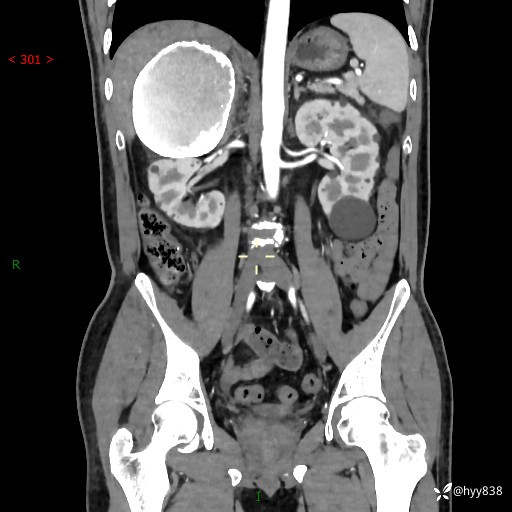

性别:男

年龄:50岁

简要病史:夜尿增多半月,发现肾功能异常1天,超声发现腹膜后占位

腹部CT平扫+增强

腹膜后肿物 (22)